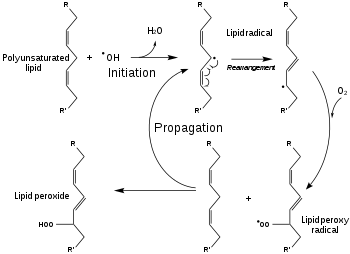

The mechanism of action for sonodynamic therapy is the use of low-intensity ultrasound through the use of focused mechanical waves to create a cytotoxic effect. However, SDT itself is non-thermal, non-toxic, and is able to non-invasively penetrate deep into tissue compared to other delivery methods such as photodynamic therapy. SDT is often performed alongside the use of a sonosensitizer such as porphyrin, phthalocyanines, xanthenes, and antitumor drugs.[17] Ultrasound waves are also classified as acoustic waves, and the effect they have on the tissue of application can be described by a process called cavitation. Cavitation occurs as a specific interaction between ultrasound and aqueous surroundings and causes gas bubbles to break upon exposure to particular ultrasonic parameters, thus promoting penetration of the therapeutic into the biological tissues by generating cavities near the edge of the membrane.[18][1] Cavitation can be broken down into stable and inertial cavitation. In stable cavitation, the oscillation of gas bubbles causes the environmental media to intermix.[1] In inertial cavitation, gas bubbles increase in volume and almost reach their resonance volume, swelling before aggressively collapsing.[1] The implosion of vesicles results in a drastic temperature and pressure change, thereby increasing the cell membrane's permeability to various drugs.[1][19] Microbubbles are created by the acoustic waves from the ultrasound that expand and collapse, releasing energy, bringing the sonosensitizer into an excited state, and generating a ROS. The cavitation of this gas bubble can form the ROS with different methodologies such as sonoluminescence and pyrolysis.[1] Apoptosis results from the formation of ROS and mechanical forces of SDT through membrane disruption in a process called lipid peroxidation. Necrosis is also a potential result of SDT.

Lipid Peroxidation

In addition to chemical methods, mechanical properties of the acoustic wave generated from the ultrasound can assist in initiating cytotoxic effects. This occurs through disruption of the membrane with a hydrophobic sonosensitizer. The mechanical disruption of the membrane causes a process called lipid peroxidation and adjustments to the cell membrane can change cell drug permeability.[1][29] Both sonochemical and sonomechanical methodologies are used to generate ROS and release cargo from vesicles for applications such as tumor targeting.